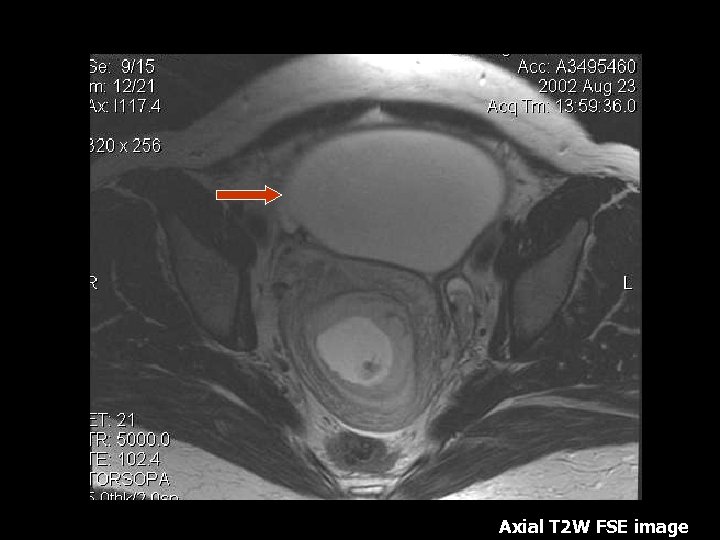

Ovarian Torsion • Fifth most common gynecologic diagnosis(8). • Symptoms – Abdominal pain, nausea and vomiting(8). • Early diagnosis can salvage ovarian function(10%)(8). • Torsion produces circulatory stasis, initially venous, then progresses to arterial(9). • Predisposing factors include ipsilateral adnexal mass, usually benign(9). • Teratoma is the most common benign neoplasm(9).

Torsion • • • MRI findings: Tube thickening(84%) Ovarian cystic mass(76%) Ascites(64%) Deviation of the uterus(36%) Less Common: Hemorrhage and hemoperitoneum

Axial T 2 W image